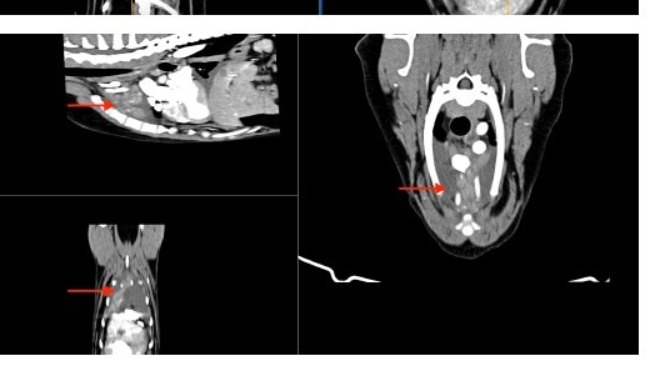

Zwykłe badanie profilaktyczne, a wyszło: podniesiony kortyzol, powiększone węzły chłonne, pobudzona śledziona i płyn w jamie opłucnowej.

Badania moczu, badanie krwi, USG jamy brzusznej, echo serca, rtg, wizyta onkologiczna.... To wszystko co już mamy za sobą i nadal nie wiadomo co się z Atenką dzieje i nie wiadomo jak ją leczyć. Wykluczony został zespół Cushinga. Wykluczone zostały choroby serca. Podejrzenie chłoniaka na razie nie zostało potwierdzone. Diagnostyka trwa dalej, a koszty rosną w przerażającym tempie. Przed nami tomografia oraz biopsja śledziony, biopsje węzłów chłonnych, badanie cytologiczne płynu z jamy opłucnej. To koszt minimum 3000 zł.